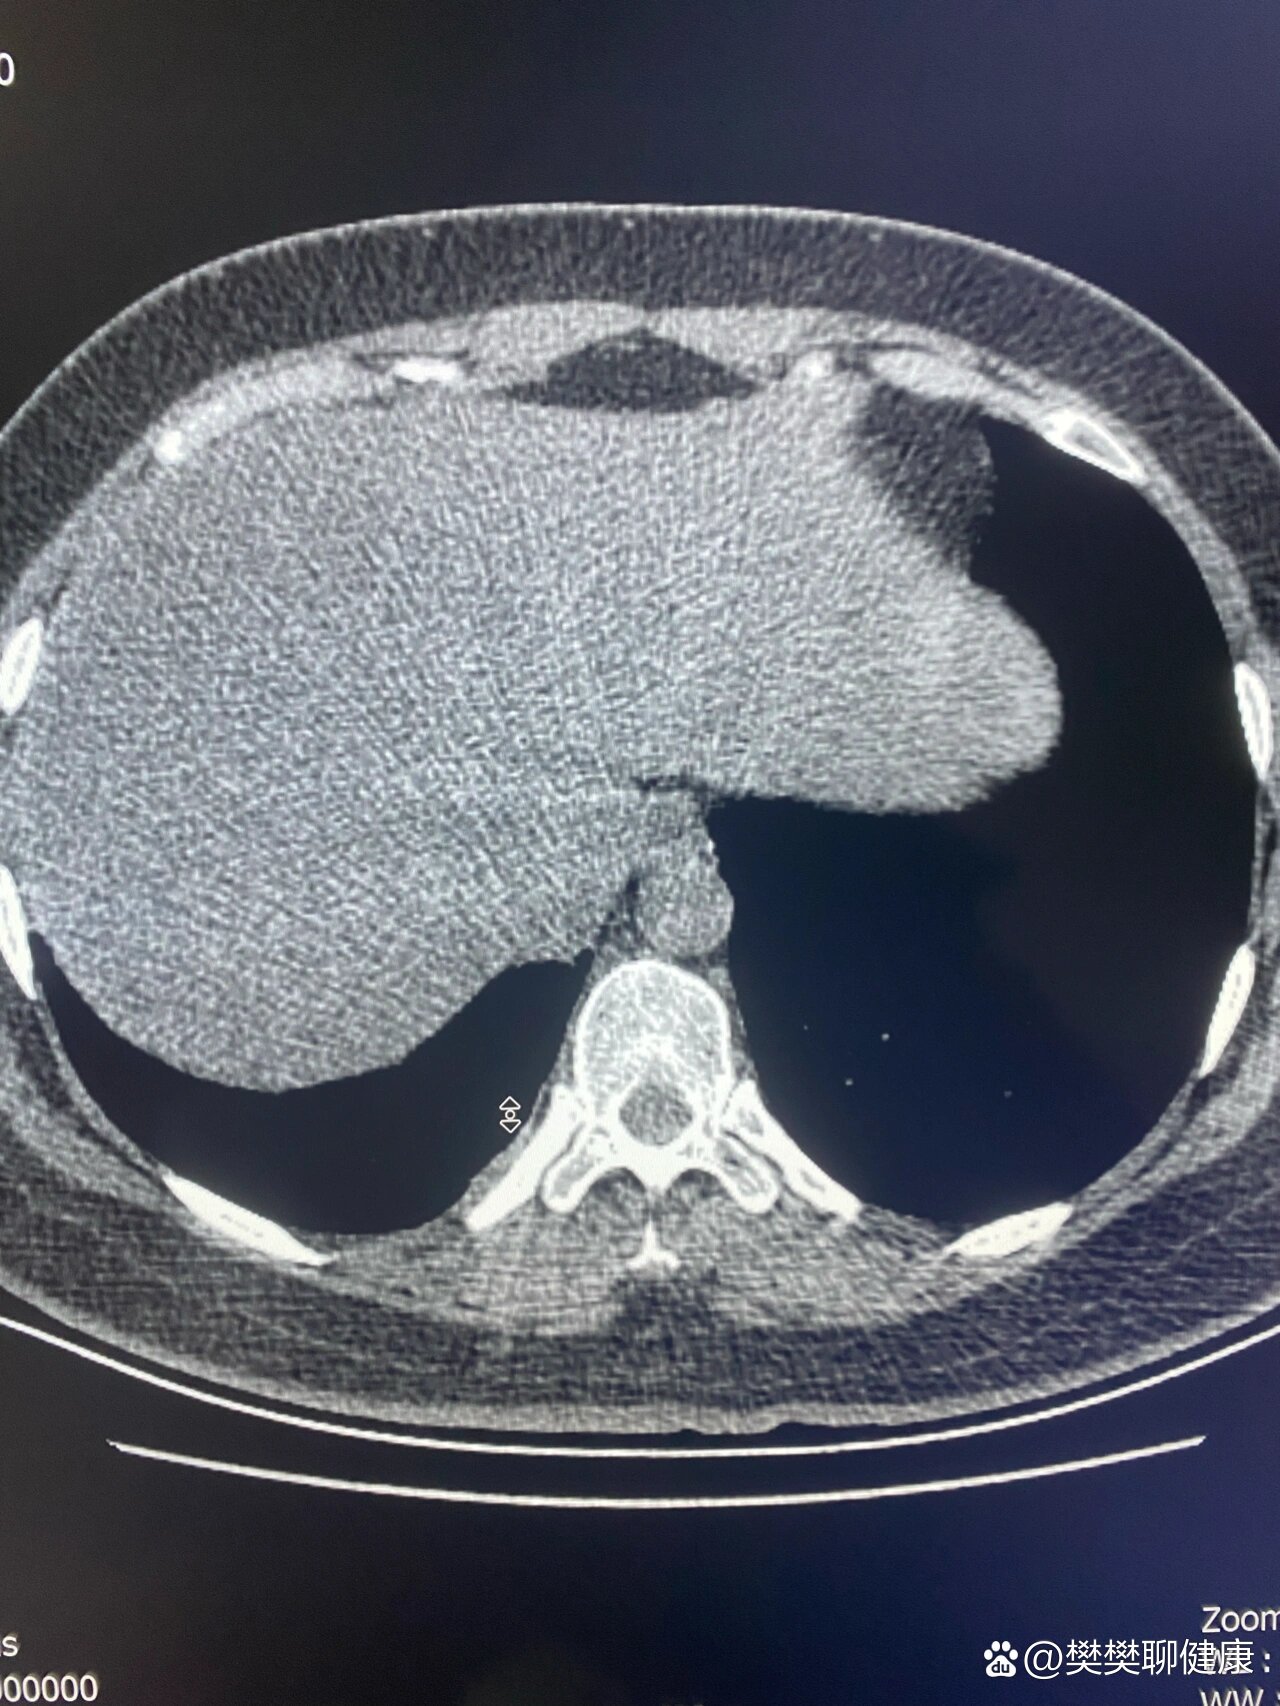

2、胸膜增厚通常无法自行痊愈胸膜增厚多由慢性疾病引发,常见于慢性胸膜炎慢性阻塞性肺疾病慢阻肺等患者其本质是胸膜组织因长期炎症刺激或纤维化反应,导致胸膜层厚度增加弹性下降这一过程具有不可逆性,目前医学上尚无特效方法使增厚的胸膜完全恢复至正常状态临床中,胸膜增厚常通过胸部CT检查发。

3、一般情况下胸膜增厚不会自愈,但因为多数患者症状较轻,也不需要特殊治疗少数明显影响肺呼吸功能的患者,需要手术治疗胸膜增厚是指胸膜受到刺激以后,纤维蛋白沉着和肉芽组织增生而致纤维化,使胸膜厚度增加的现象,可为局限性和广泛性广泛性的壁层胸膜增厚,可以使肋间隙变狭小,胸廓缩小,进而影响肺。

16、但完全恢复至正常状态的概率较低,尤其是病程较长或反复感染者2 遗留表现的原因若胸膜肥厚伴随严重纤维化或钙化如结核性胸膜炎后遗症,或未及时治疗导致慢性炎症持续刺激,胸膜可能形成不可逆的增厚此时,影像学检查如胸部CT仍可见局部胸膜增厚或粘连,但患者可能无显著症状3 症状与治疗。